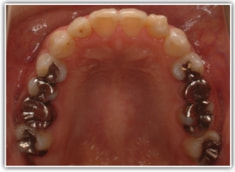

反対咬合ケース

治療法:表の矯正(T21ブラケット)

治療後(1年6ヶ月後)